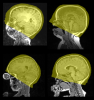

Field-of-view mismatch in different subjects' images poses additional challenges to the streamline analysis of large-scale brain MRI datasets.

We release an atlas-based FOV normalization tool. This tool automatically truncates the FOV to that of the MNI152 atlas', which includes the whole brain, the skull, and ends 10-15mm inferior to the most inferior voxel in the cerebellum. This tool runs in linux platform (command line). It has been extensively validated in hundreds of MRIs, acquired from various scanners (Philips 1.0T, Siemens/GE 1.5T/3T), in various imaging sites, with various scanning FOVs, and from subjects of various ages (infants, neonates, adolescents, young adults, elderly).

We have quantitatively shown that this FOV normalization significantly improves the accuracy and success rate in streamline analysis of neuroimages in the very first steps (e.g., skull stripping, inter-subject registration, etc).